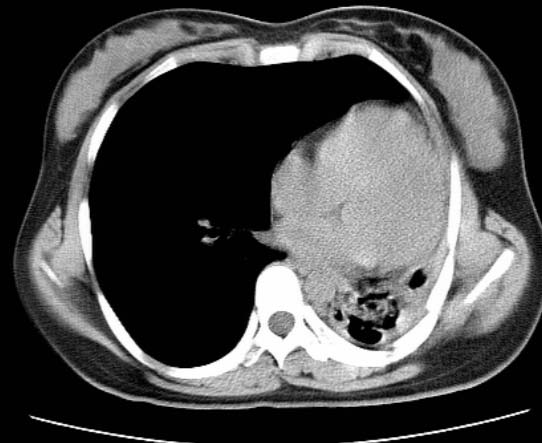

标题: CT25648:求教:是肺发育不全还是结核?

女  20岁。一月前咳血,诊“肺结核”抗痨治疗一月后,咳血停止,现复查。病人精神好。前后ct片对比未见明显变化。既往体检“正常”

1)考虑左肺结核并肺不张、支气管扩张。2)纵隔疝。

考虑左肺结核,左肺毁损,纵膈左偏,既往体检正常不可靠,tb一个月也不会这个样子的,有钙化,应该病程较长,冰冻三尺非一日之寒!

左肺发育不全。

结核,左肺毁损。